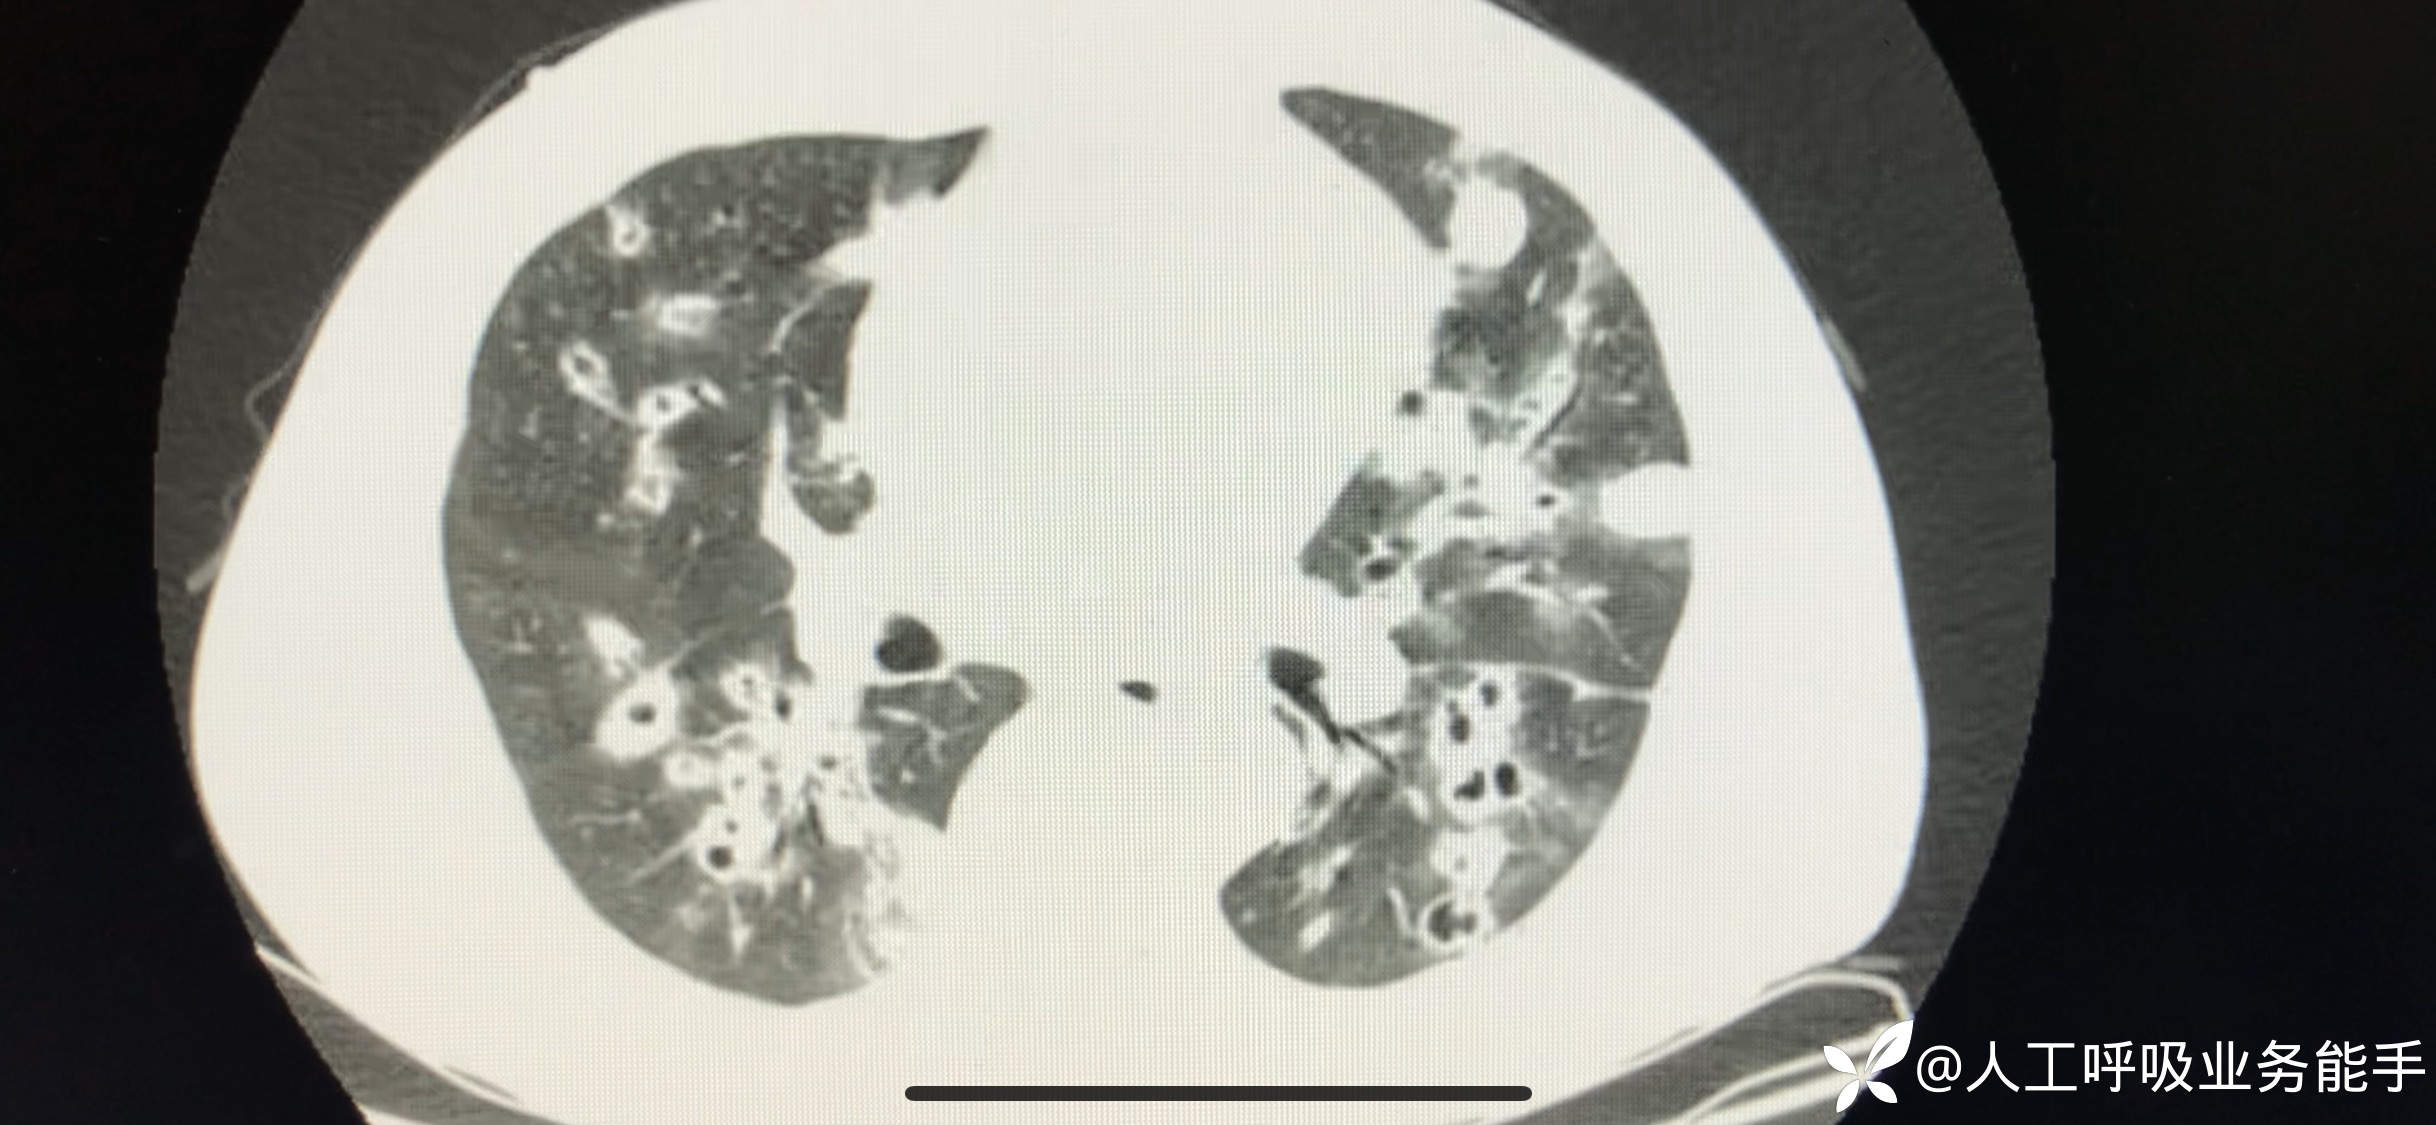

初诊影像:

支气管镜检查后确诊